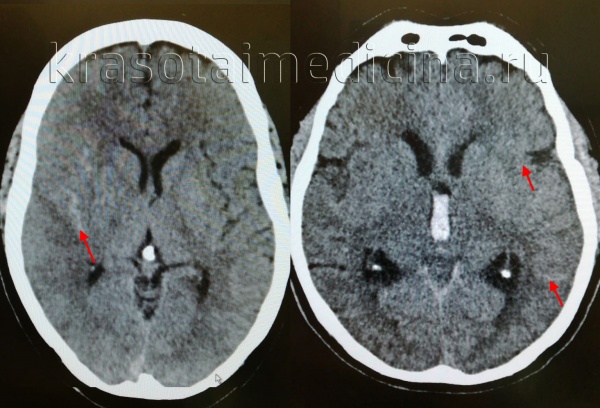

2. КТ при травматическогом субарахноидальном кровоизлиянии (тСАК):

• Бесконтрастная КТ:

о Высокая плотность в субарахноидальном пространстве/цистернах

о Гиперденсная кровь в межножковой цистерне может быть единственным признаком слабовыраженного САК

о Признаки идентичны аневризмальному САК за исключением локализации:

- В области ушибов, субдуральной гематомы

- Борозды конвекситальной поверхности > базальные цистерны

Распространение крови при травматическом САК:

- Обычно сочетается с другими признаками ТЧМТ (отек, очаги ушиба, эпидуральные, субдуральные гематомы)

- Кровь расположена более поверхостно вокруг корковых структур